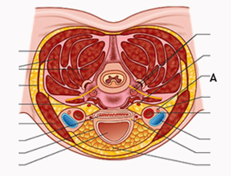

Q1. The image below highlights the jugular foramen. Which of the following structures do not pass through the marked structure “A”?

- Glossopharyngeal nerve

- Accessory nerve

- Vagus nerve

- Hypoglossal nerve

Answer: D